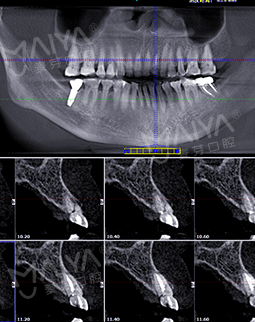

2018年4月3号 第一次来麦芽拍片

我很信任郑教授带领的种牙团队,而且现在不比当年了,科技也发达了,尤其是麦芽口腔的环境、设备、服务这些都感觉很高大尚,拍个片子都是三维的,不到10分钟,片子就呈现在医生的电脑上了,在几十年前哪有这种设备啊。

郑院长带领的医师团队,给我讲片子很清楚,说我的左上2牙齿出现松动,但是牙龈状况良好,可以告诉我牙齿即拔即种,无需等待3个月拔牙愈合期,避免二次创伤性伤口,他们以修复为导向,尤其我这种前牙的,还要兼顾咀嚼的咬合功能与美观性,虽然不太懂这个技术,但我还是很信赖郑院长的团队的,也感叹现在技术的先进。方案定制完成后,3D口扫取模,就跟牙刷大小一样的东西在口内扫一下,为了制定导板,种牙的时候更方便。